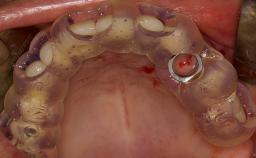

This learning module will provide an overview of the most commonly seen intraoperative and postoperative complications associated with sinus floor elevation and will discuss management in terms of preventative measures as well as treatment strategies.

• intraoperative complications of lateral window sinus floor elevation

• intraoperative complications of transcrestal sinus floor elevation

• postoperative complications of sinus floor elevation